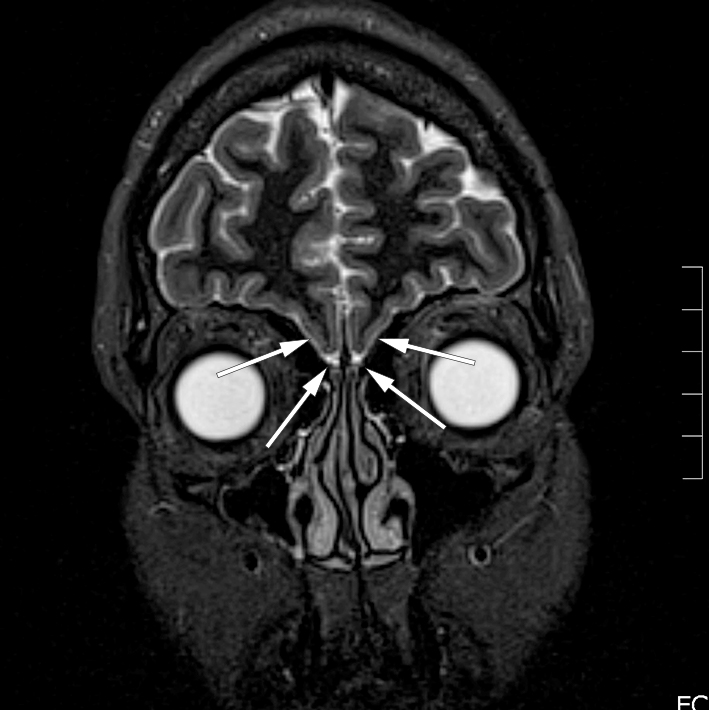

Anamnese med anosmi, manglende pubertetsutvikling og lave nivåer av kjønnshormoner før substitusjonsbehandling gav mistanke om Kallmanns syndrom, og hun ble henvist til ny MR caput med spørsmål om sulcus olfactorius og bulbus olfactorius var til stede. MR viste mangel på disse bilateralt (figur 1). Anatomiske forhold var dermed best forenlig med Kallmanns syndrom. Hun ble henvist til genetiker og endokrinolog, som ikke fant annen relevant patologi.